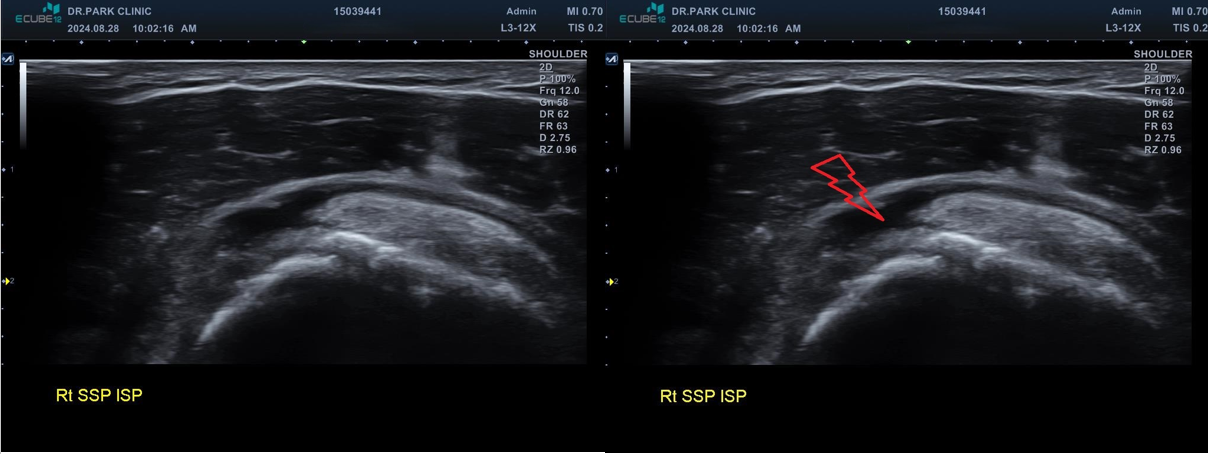

마지막 초음파에서는 어깨 극상근의 파열 소견이 관찰되고 있습니다. 정확한건 mri 를 찍어봐야 하겠지만 찢어진 길이와 정도로 봐서는 수술이 필요한 극상근 전층파열로 생각이 됩니다.

나 : 초음파상에서 어깨 극상근이라는 힘줄 파열이 관찰되네요. 이게 제일 문제입니다

나 : 수술 여부는 MRI를 찍어야만 정확히 결정되는 거지만.... 초음파에서 이정도 파열인 경우 보통 수술 하는게 좋습니다.